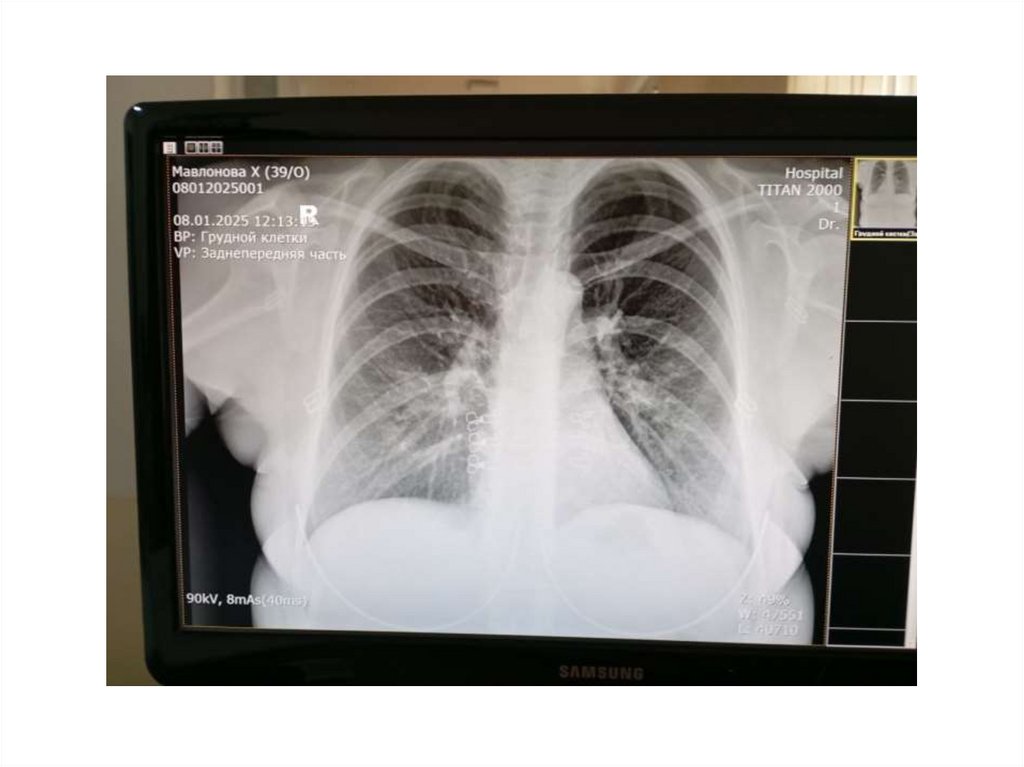

Bemor Mavlanova Xurshidabonu • 24/09/1986 yil

• Bemor Mavlanova Xurshidabonu

• 24/09/1986 yil

• 2024-yil 20-apreldan Latent tuberkulyoz bilan

davolangan

• 2024-yil 24-oktyabrdan ikkala o’pkalar o’choqli

tuberkulyozi infiltratsiya davri BK abc bilan 1qator dorilarini ichishni boshladi